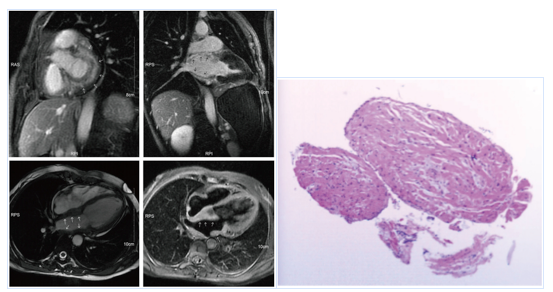

然后对患者进行心脏磁共振(CMR)检查(图3),确认左房壁显著增厚,左房和右房没有扩大,三重反转恢复序列(IR)在延迟扫描上显示更均匀的高信号和显著的不均匀增强。无心室肥大、主动脉或肺动脉扩张或狭窄,左心室射血分数为66%。

图3. CMR显示左房壁明显增厚

图4. 左心房EMB显示心肌和纤维组织增生,局部有不规则的淋巴样细胞

为了明确诊断,在患者家属的同意下,进行了心内膜心肌活检(EMB)检查和临时起搏器植入。左心房样本的组织学检查表明心肌和纤维组织增生,局部有不规则的淋巴样细胞(图4)。免疫组化染色显示肿瘤细胞CD3、CD5和CD8弥漫阳性,CD2、CD7、CD4和颗粒酶B散在阳性,ki-67增殖指数达30%。然而,肿瘤细胞的CD20、CD56、CD10、BCL6、PD-1、CD21、CXCL13、CD30、ALK、CD99和P53均为阴性。T细胞相关标记物CD3+、CD5+、CD7+、CD2+、B细胞相关标记物CD20和CD21阴性、细胞增殖相关标记物ki-67 30%+、CD4+/CD8+。与血管免疫母细胞T细胞淋巴瘤不同,本病例CD10、BCL6、PD-1和CXCL13阴性,与间变性大细胞淋巴瘤相关的标记物CD30和ALK阴性。上述标记物表明本例的病理免疫表型为非特异性外周T细胞淋巴瘤,而非其他类型的淋巴瘤。患者随后被转移到血液科接受化疗。